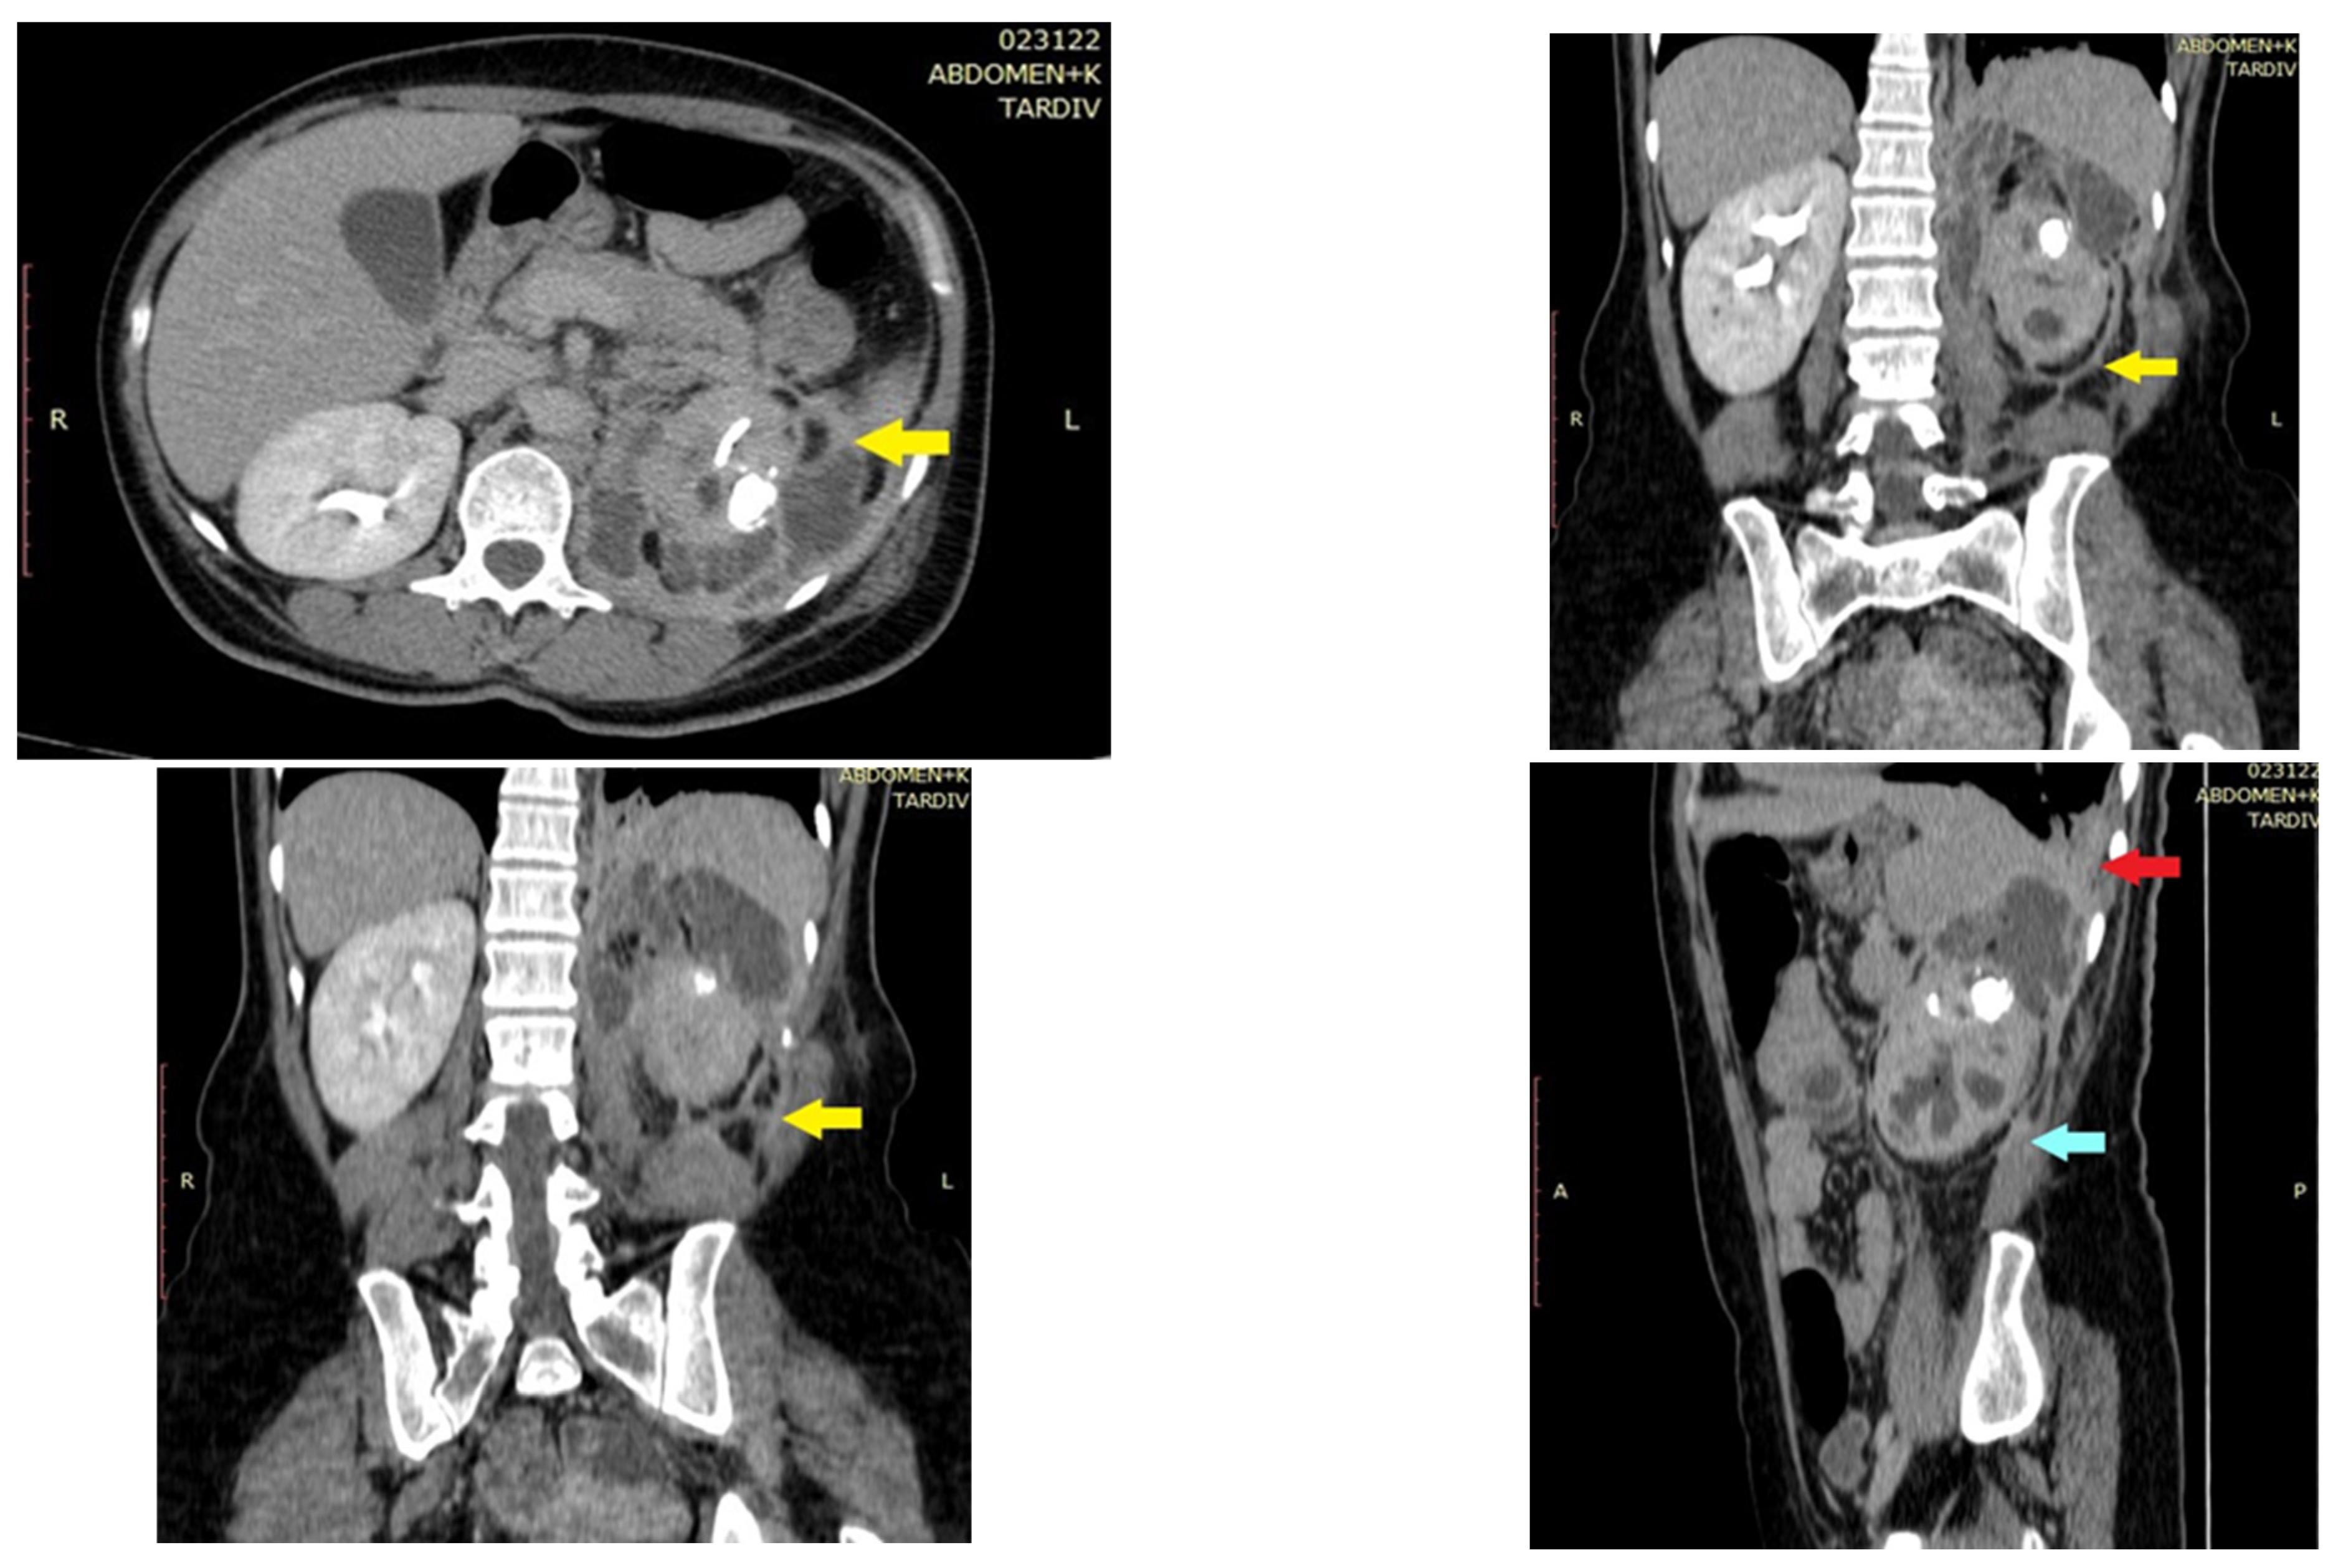

2. Case Report